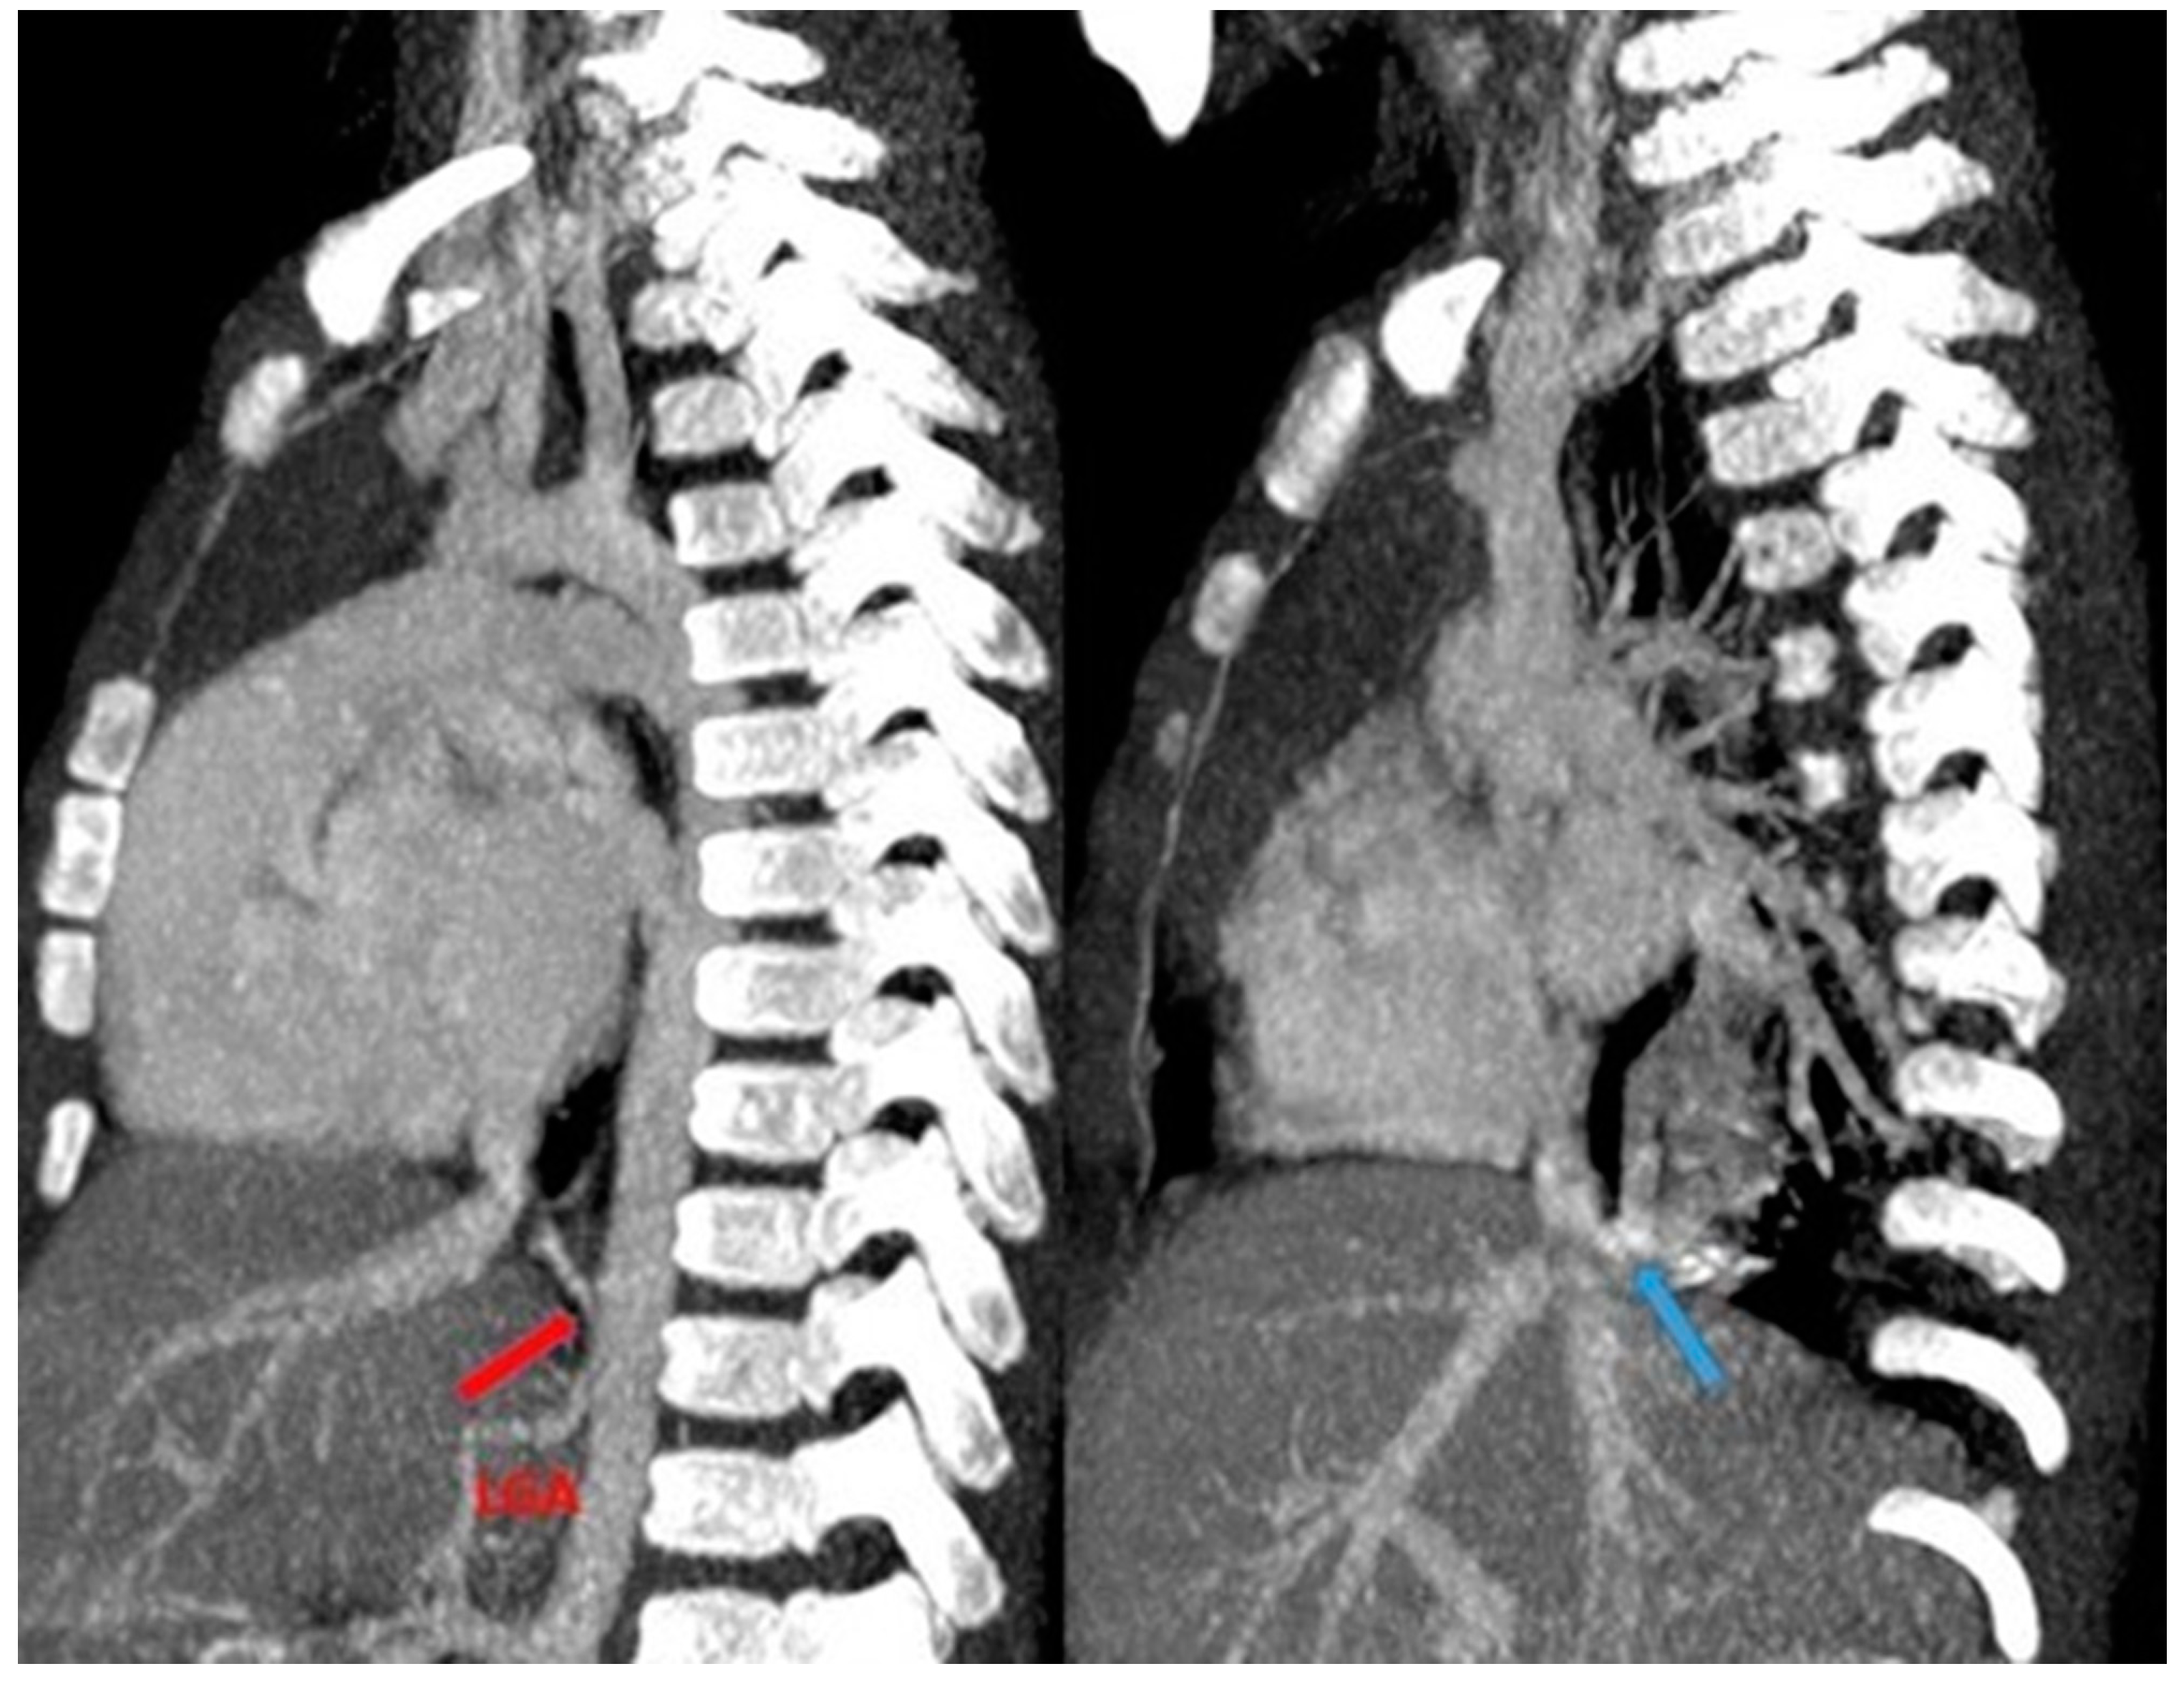

3.6.1. Pulmonary Sequestration